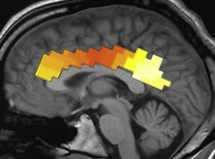

Con técnicas avanzadas, los investigadores localizaron las lesiones cerebrales sufridas por los participantes en el estudio tras su operación, y paralelamente evaluaron la intensidad de la ST en los pacientes antes y después de la cirugía.

Este método, según declararon los científico, ha permitido explorar posibles cambios en la ST inducidos por lesiones cerebrales concretas, así como la causalidad de las estructuras frontal, temporal y parietal en las diferencias que había entre los individuos en cuanto a la ST.

Los investigadores descubrieron así, que aquellos pacientes a los que se les había practicado la cirugía en la parte posterior del cerebro presentaban una ST más acusada tras la operación. Esto no fue lo que sucedió con los pacientes afectados en la zona anterior del cerebro.

El hecho de que los tumores cerebrales situados en distintos puntos del cerebro tengan efectos diversos en la ST individual supondría, según los científicos, que se ha establecido una base neuronal de la que dependerían los estilos cognitivos y emocionales que caracterizan la espiritualidad de cada persona.

Esta relación sería la siguiente: el daño sufrido por las zonas parietales posteriores del cerebro provoca rápidos cambios relacionados con la conciencia autorreferente transcendental. Según esto, puede que una disfunción de la actividad neuronal parietal sea la responsable de la alteración de los comportamientos religiosos y espirituales y de la actitud ante ellos.

Así, por ejemplo, en investigaciones neurológicas recientes se han descubierto las zonas del cerebro implicadas en las experiencias místicas e, incluso, se ha llegado a presentar el primer mapa del cerebro místico en prensa.